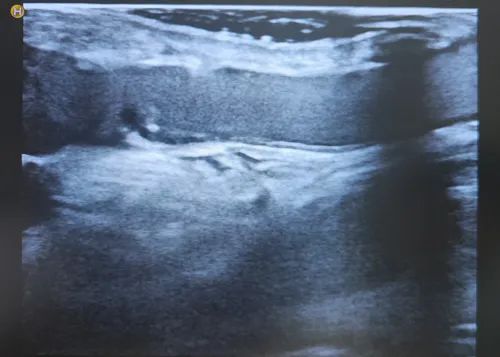

在(DSA)介入引導(dǎo)下

送球囊至血管狹窄處

用壓力泵對球囊加壓

將血管閉塞部位成功打開

較為狹窄處的血管

內(nèi)徑僅為1mm左右